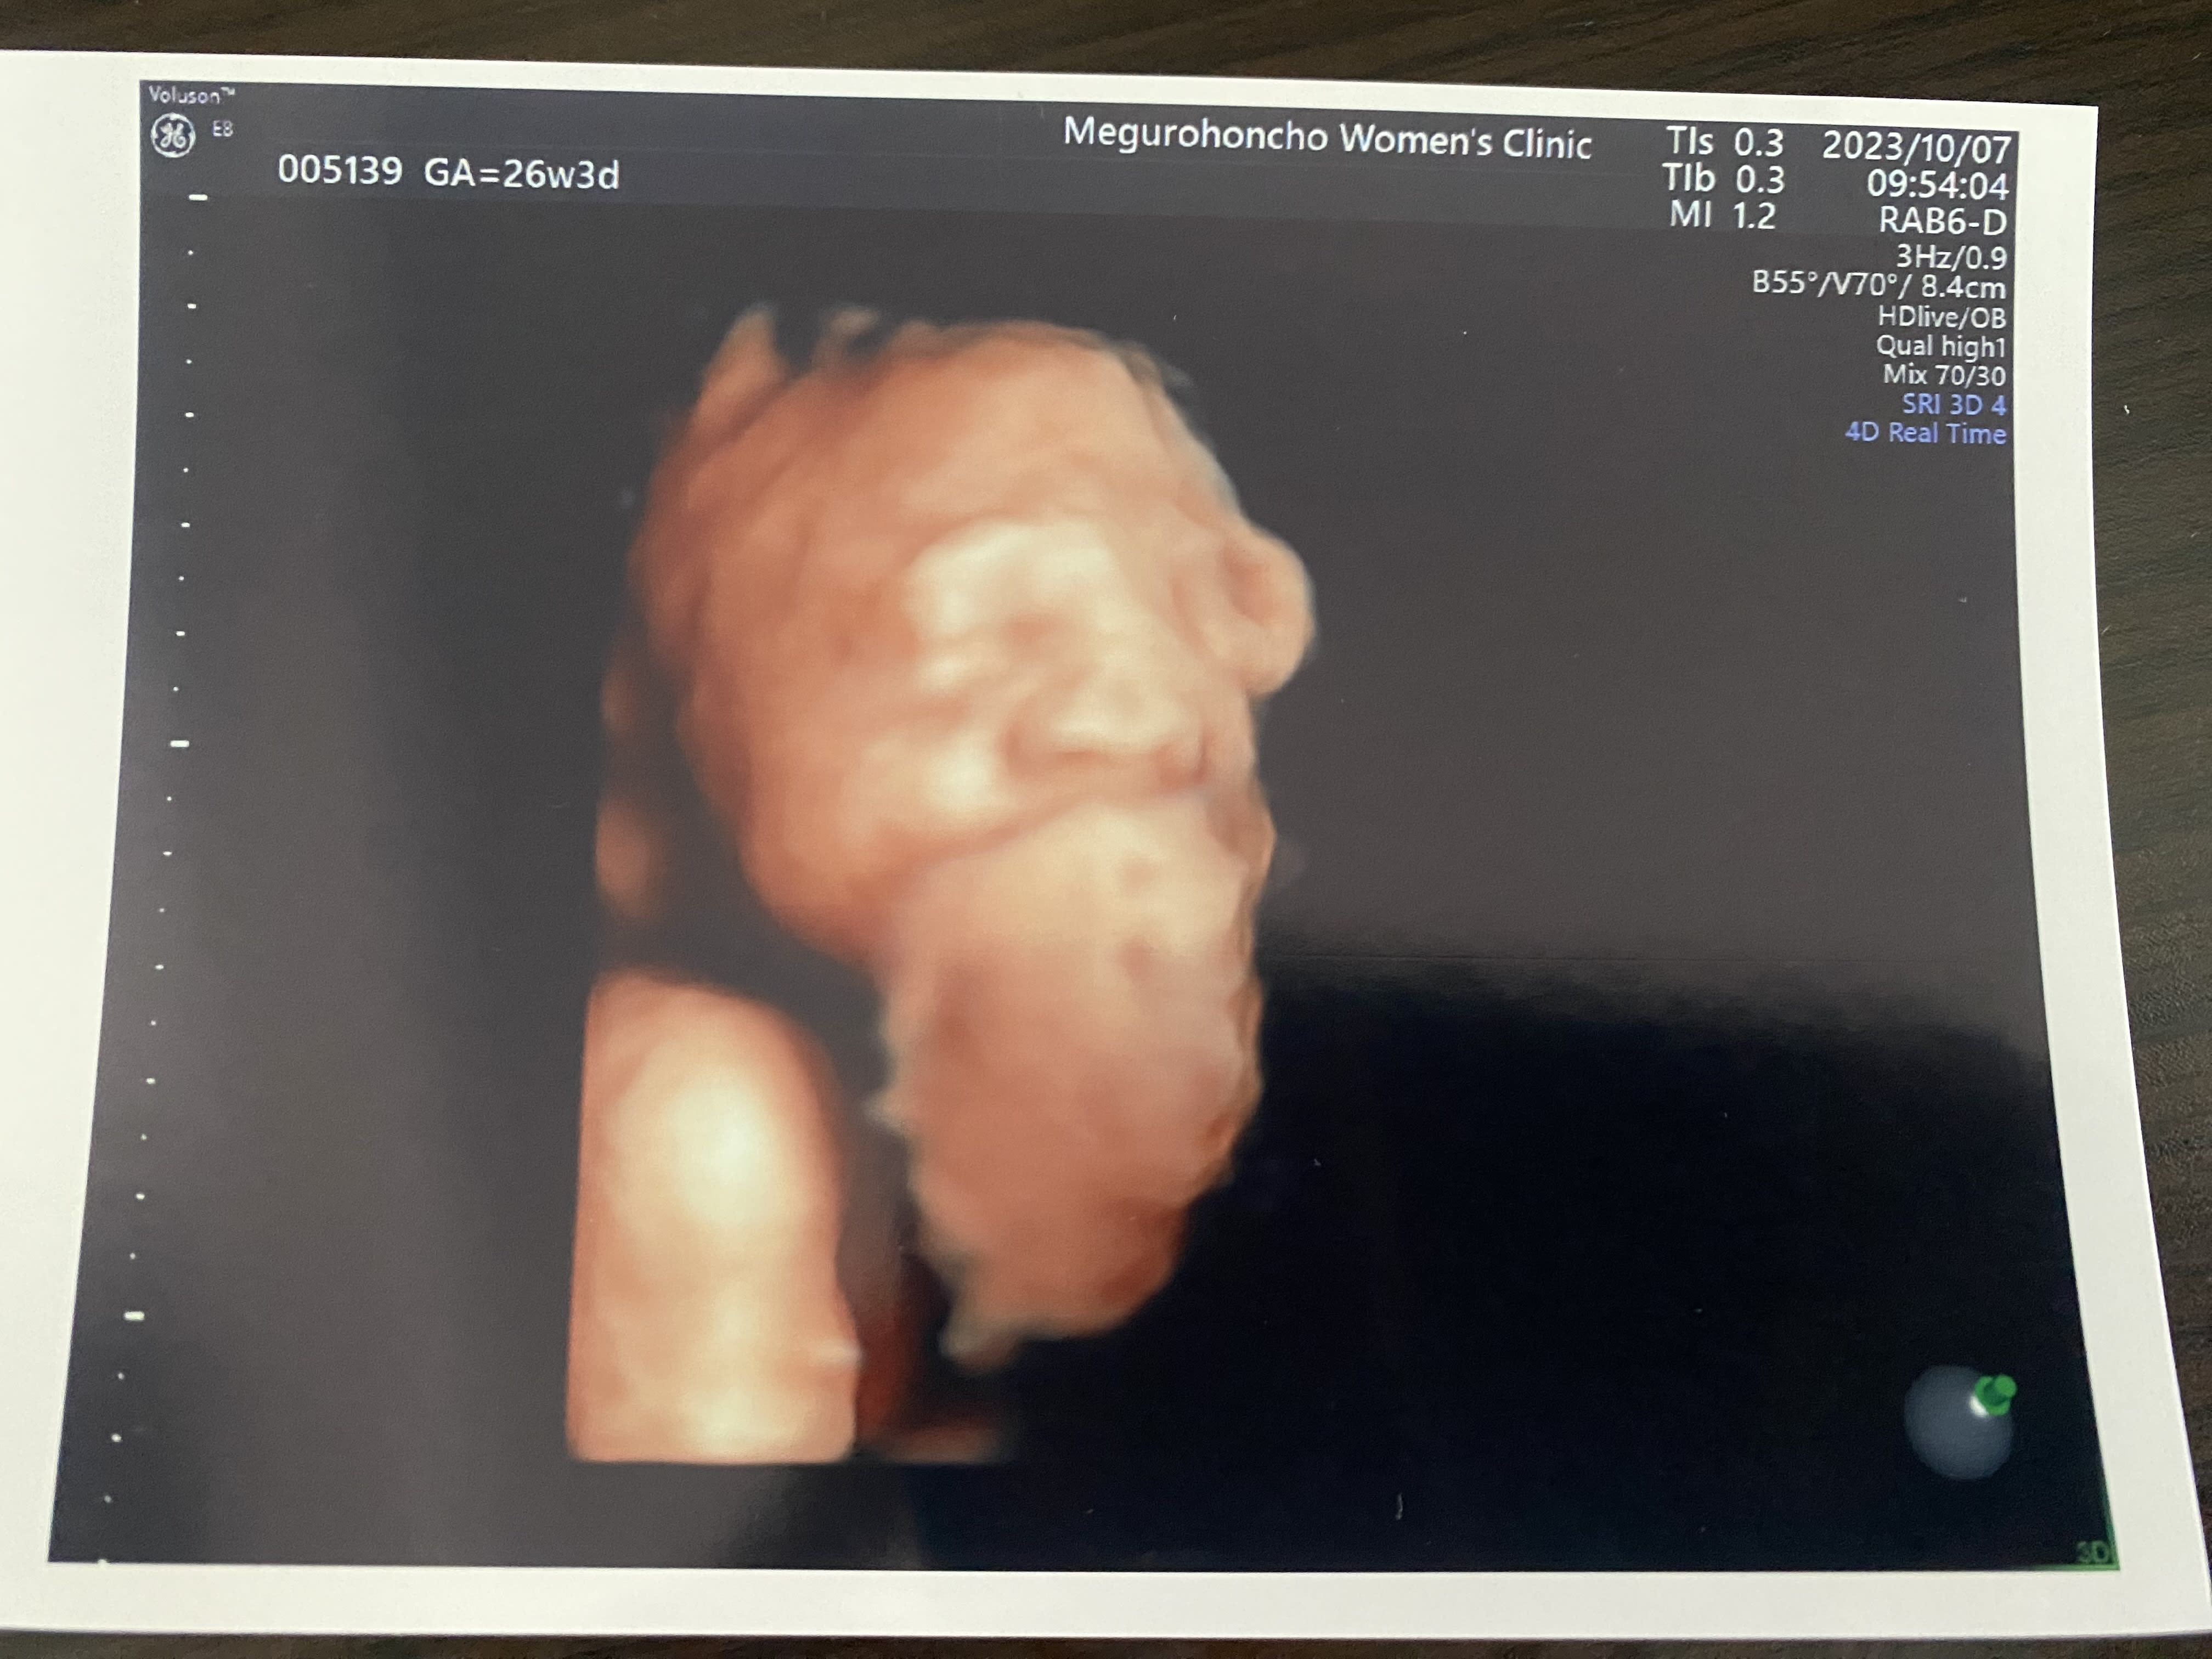

26週の4Dエコー 手で顔を隠してるみたい。顔がもっと分かるようになってきたかな? ジウンちゃんとKatriがレオくんに可愛いギフトをくれたよ!

07 Oct 2023